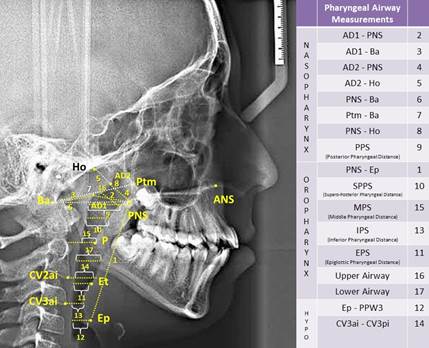

In study, 35 cephalometric points (Figure 1), 8 cephalometric planes, and 30 cephalometric measurements (Figure 2) were used. In the cephalometric analysis; 5 craniofacial, 8 nasopharyngeal, 7 oropharyngeal, 2 hypopharyngeal (Figure 3), 9 hyoid measurements (Figure 4) and 4 area measurements (Figure 5) were used.